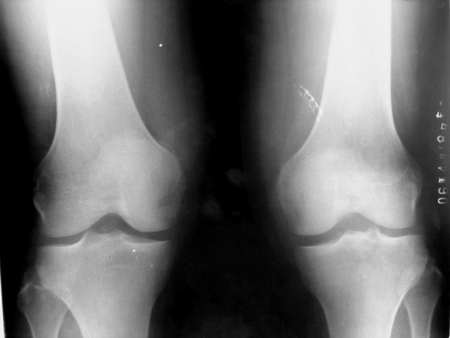

男,45。骑摩托车摔伤左膝肿痛三天,浮髌(+),活动受限。请大家看看片子有问题吗?

图像不是很清晰,除关节肿胀外未见明显异常。

侧位片股骨远端与髌骨重叠部见团块壮骨密度影,考虑股骨远端撕脱骨折

可疑左胫骨平台骨折.建议ct检查.

左胫骨髁间隆突骨折,建议ct检查!!

考虑胫骨平台骨折

不清晰,且左右不明确.胫骨平台上隐约可见一小骨片,

应该是左髁间突隆骨折?

是平台骨折,5楼强

片的质量不是很好,髌骨前下角好像有透亮线?

左侧胫骨平台骨折

像是胫骨髁间嵴骨折!

好象是胫骨平台骨折

关节积液及股骨远端可疑骨折